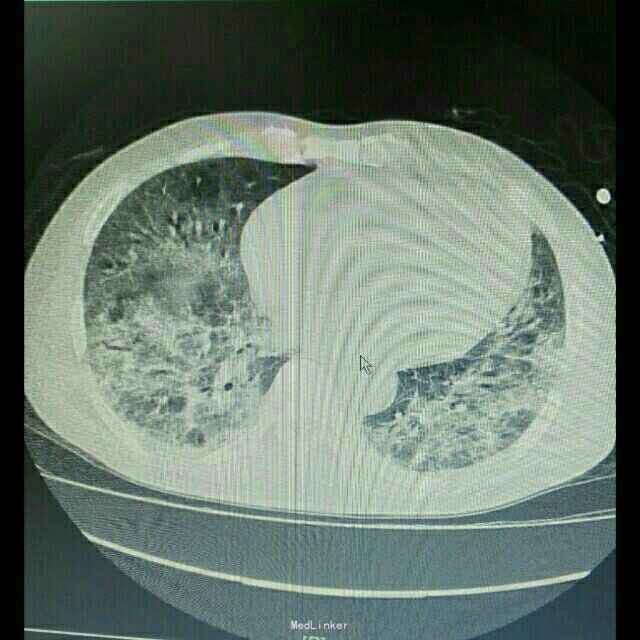

主诉:肾移植术后2月,发热、咳嗽5天 病史:患者男,45岁,因尿毒症于2月前在外院行异体肾移植术,手术过程顺利,术后恢复良好,移植肾功能稳定,服用FK506+MMF+Pred免疫抑制维持治疗。患者术后未规律门诊随诊,有情况变化时常电话联系行手术的医院,在术后免疫抑制剂服用剂量较大,为MMF1gBid+FK506 3.5mgBid+Pred25mgQd,其中FK506平时维持的浓度约10ng/ml。5天前开始出现发烧,最高体温38.8℃,自服“降温药”后体温可下降,伴咳嗽,无胸闷气促,无诉其他不适。

辅助检查:患者入院后症状进行性加重,入院2日后出现胸闷、气促,动脉血气分析提示氧分压为59mmHg,胸部CT提示双肺严重弥漫性炎症。

诊断:肺部感染;异体肾移植状态 治疗:患者入院后积极抗感染治疗,检查胸部CT和血气分析后给予吸氧等对症治疗,抗感染方案为泰能+伏立康唑+科赛斯+更昔洛韦,并停用所有口服免疫抑制剂,改为甲强龙40mgQd静脉滴注,患者治疗后肺部感染无明显好转,2日后转入ICU进一步治疗。